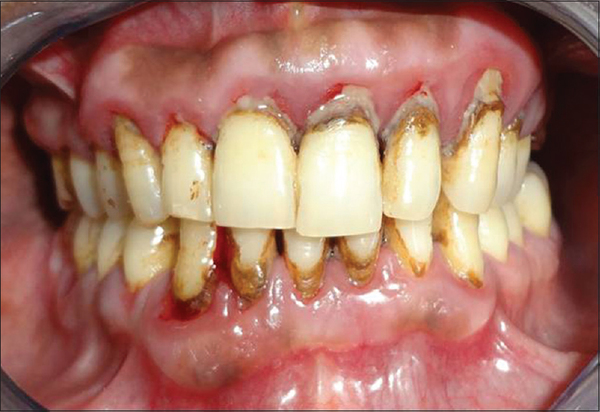

Вирусный гингивит

Развивается из-за наличия общей инфекции, которая попала в организм вследствие нехватки витаминов и снижения иммунитета.

Фото 3. Причиной возникновения вирусного гингивита являются вирусы простого герпеса и цитомегаловирусная инфекция.

Заболевание может протекать как в хронической, так и в острой форме.